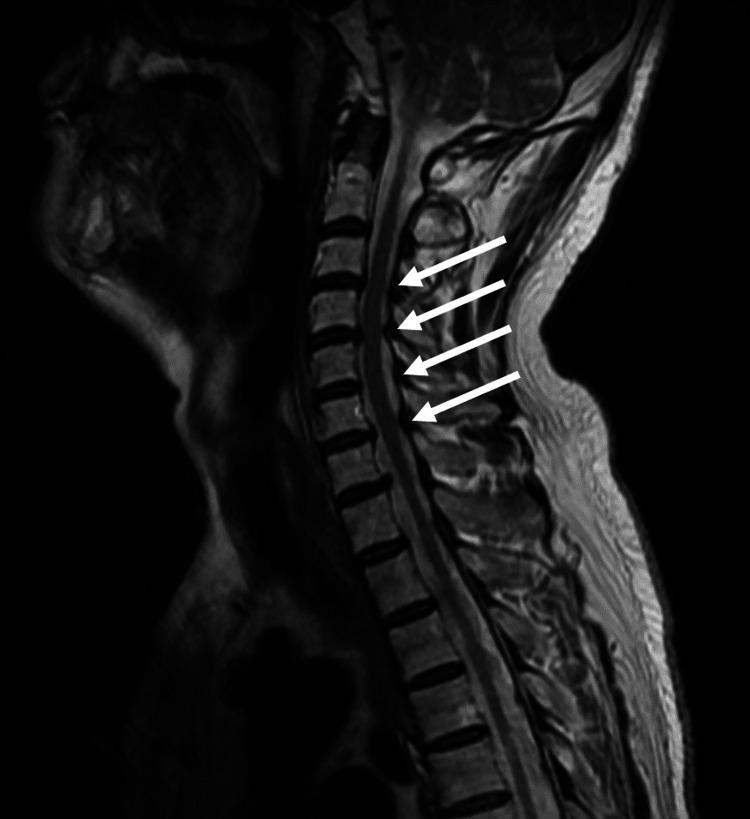

Bilateral diaphragmatic nerve paralysis due to cervical spondylosis is an extremely rare condition with only one previously reported case. We present a 64-year-old Japanese male with a history of left diaphragmatic nerve paralysis who developed sudden nocturnal dyspnea. Physical examination revealed orthopnea and type 2 respiratory failure. Imaging studies showed bilateral diaphragmatic elevations and cervical spine stenosis at C3/C4 and C4/C5 levels. Pulmonary function tests demonstrated a significant reduction in vital capacity, particularly in the supine position. After excluding other potential causes, the diagnosis of bilateral diaphragmatic nerve paralysis secondary to cervical spondylosis was established. The patient was successfully treated with noninvasive positive pressure ventilation (NPPV) and showed gradual improvement in symptoms and diaphragmatic function over three years of follow-up. This case highlights the importance of considering cervical spondylosis as a potential etiology for bilateral diaphragmatic nerve paralysis and demonstrates the effectiveness of NPPV in managing this rare condition. Regular monitoring and long-term follow-up are crucial for optimal management of these patients.